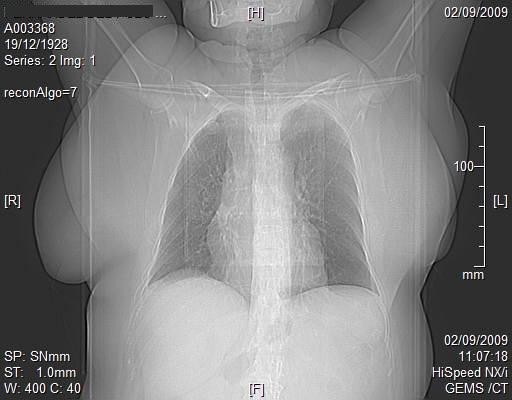

Tomografía Computada: Imágenes Superiores a los Rayos X

La tomografía computada (CT) combina la ciencia de los rayos X con la tecnología computarizada para producir imágenes más enfocadas e informativas que los rayos X tradicionales. Las tomografías computadas producen imágenes claras de los huesos, tejidos blandos, órganos, discos intervertebrales y médula espinal. Las imágenes pueden reproducirse en tonos de negro/gris/blanco o en color. Para mejorar la imagen puede inyectarse al paciente un medio de contraste (tinción) durante la prueba.

Durante una tomografía, una serie de rayos X se dirigen en ángulos específicos para atravesar la parte del cuerpo que se está examinando. Un detector del lado opuesto transmite los detalles de la exploración a una computadora, la cual analiza la información y produce imágenes transversales de esa parte del cuerpo. Las imágenes transversales o “rebanadas” se conocen como tomogramas. Las imágenes pueden mostrarse en un monitor, guardarse como archivos en la computadora, o imprimirse en película común de rayos X.